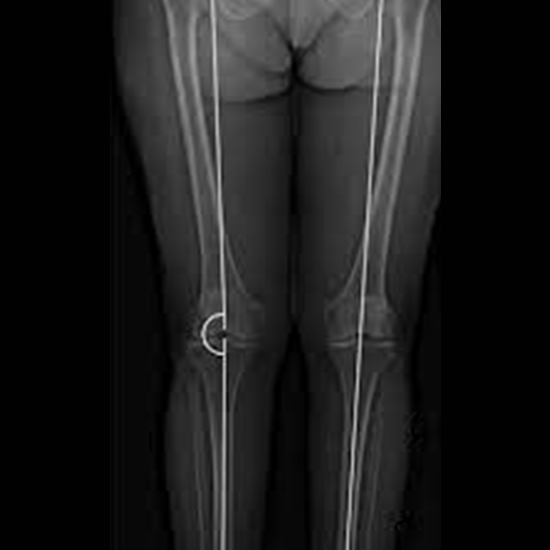

X-Ray Scanogram

A diagnostic technique known as a Scanogram Lower Limb is one that creates cross-sectional images of the lower limbs, also known as the legs, by rotating beams of X-rays.

The doctor prescribes this test to measure the length of the leg bones and detect any inequality in leg length, particularly in children.